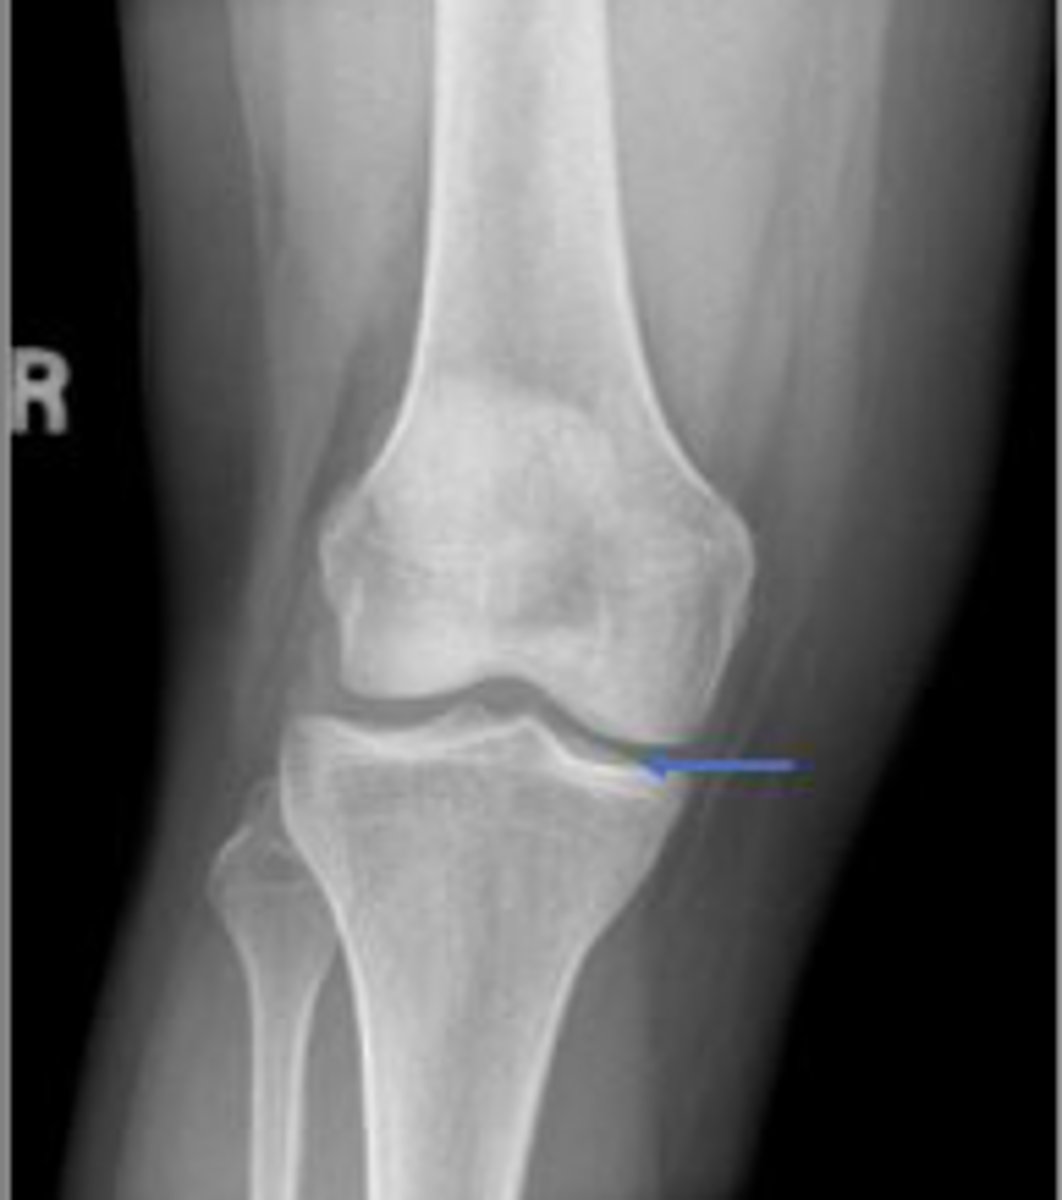

Medial femorotibial joint space of the right knee

What joint space is the arrow pointing to?

Lateral collateral ligament

What inserts at the location of the blue arrows?

Lateral collateral ligament avulsion fracture of

the right knee

What is the most significant radiographic finding?